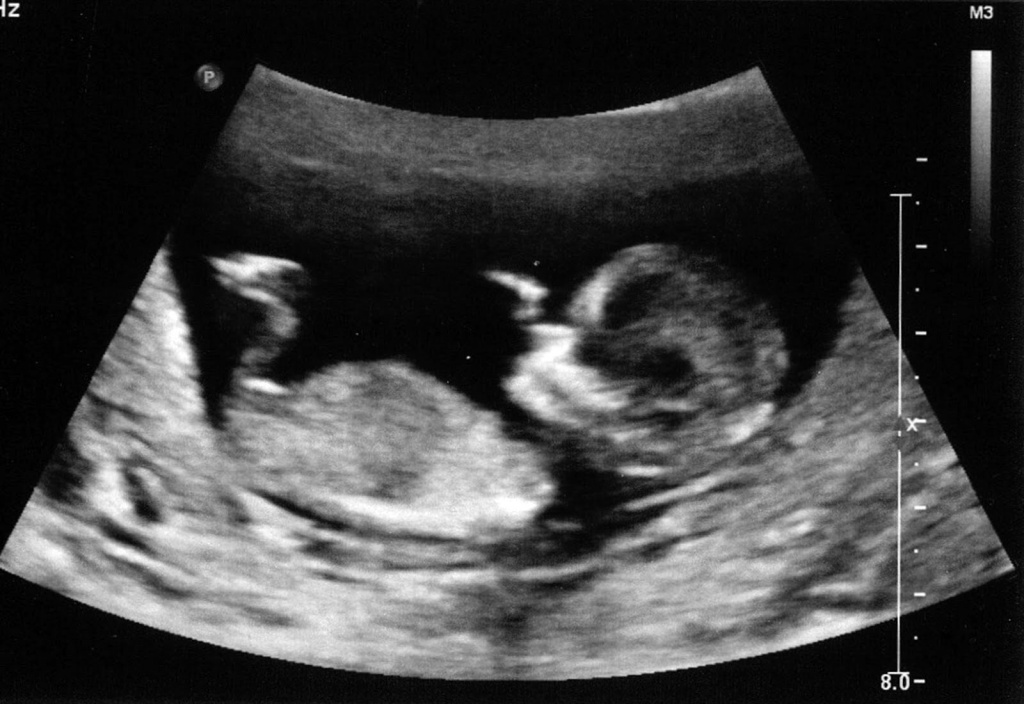

Ультразвуковое исследование, проводимое на 4-5 месяце вынашивания ребенка, обычно дает достоверный ответ на вопрос родителей о том, девочка будет или мальчик? За исключением моментов, когда малыш разворачивается в утробе матери спиной и занимает положение, когда увидеть его половые органы специалистам на УЗИ становится невозможно.

УЗИ – самый безошибочный метод определения беременности

Совпадение каких-либо признаков – это всего лишь небольшая вероятность беременности девочкой. Современная медицина и профессиональное оборудование могут ответить на ваш вопрос с точностью до 99%. Только обследование у специалистов в области медицины и УЗИ помогут вам узнать пол ребенка и родить крепкого карапуза. Ни это ли важно? Родители всегда будут рады рождению здорового малыша и неважно, кто это будет – мальчик или девочка!

Поэтому вы можете попросить специалиста посмотреть, мальчик у вас или девочка, на плановом УЗИ, которое проводят как раз между 18-й и 21-й неделями. Ультразвуковая диагностика считается основным методом определения пола ребёнка, но важно помнить, что он не абсолютно точный.

При определении пола плода по крови беременной женщины анализ можно сделать раньше: начиная с 12 недель беременности по УЗИ (или с 9 полных недель беременности по УЗИ при выполнении НИПТ). Пол будущего ребёнка можно узнать с помощью УЗИ или анализа крови беременной.